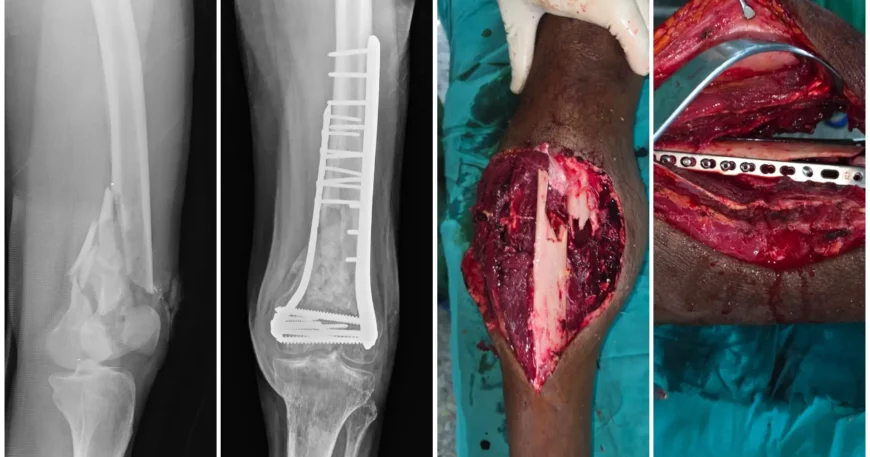

Left Distal Femur Fracture Treated with Open Reduction and Internal Fixation Using Both Column Plates and Screws | Balanku Hospital

Distal femur fractures are serious injuries involving the lower part of the thigh bone near the knee joint. These fractures often result from high-impact trauma such as road traffic accidents or falls and require precise surgical management to restore alignment and knee function.

Clinical examination and imaging studies confirmed a Left Distal Femur Fracture, involving the region close to the knee joint. These fractures require anatomical reduction to restore joint alignment and prevent long-term stiffness or arthritis.

Open Reduction and Internal Fixation (ORIF) with Both Column Plates and Screws

The patient underwent Open Reduction and Internal Fixation (ORIF) using both column plates and screws.

Careful exposure and anatomical reduction of fracture fragments

Stabilization of both medial and lateral columns of the distal femur

Rigid fixation using specially designed plates and screws

Using dual (both column) plating provides enhanced stability, especially in complex or comminuted fractures.